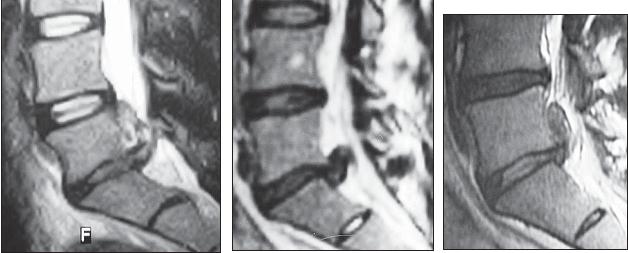

МРТ № 1

На магнитно-резонансной томографии (МРТ) № 1 — шейный отдел позвоночника, в относительно нормальном состоянии.

Шейный отдел позвоночника должен иметь нормально выраженный физиологический лордоз, не должно быть гиполордоза или гиперлордоза, а так же кифотических деформаций.

Ширина спинного мозга: сагиттально > 6–7 мм

1. Сагиттальный размер позвоночного канала на уровне:

СI 21 мм

СII 20 мм

СIII 17 мм

CIV-CVII = 14 мм

2. Высота межпозвонковых пространств:

СII < СIII < СIV < СV < СVII  СVII

3. Ширина спинномозгового канала: поперечный диаметр на уровне ножек: > 20–21 мм

МРТ № 2

На МРТ № 2 — грудной отдел в состоянии «норма»

Грудной отдел должен иметь нормальную степень кифоза (угол кифоза по Stagnara формируется линией, параллельной замыкательным пластинкам ТIII и ТXI= 25°). Позвоночный канал на грудном уровне имеет округлую форму, что делает эпидуральное пространство узким почти по всей окружности дурального мешка (0,2–0,4 см), а на участке между TVI и ТIX он наиболее узок. Сагиттальный размер: ТIХI = 13–14 мм, ТXII = 15 мм. Поперечный диаметр: > 20–21 мм.

Высота межпозвонковых дисков: самая меньшая на уровне ТI, на уровне ТVIХI приблизительно 4–5 мм, наибольшая на уровне ТХIХII.

МРТ № 3

На МРТ № 3 — поясничный отдел позвоночника. (На данном «контрольном» снимке наблюдаются остаточные явления дегенеративно-дистрофического процесса в сегменте LV-SI после устранения методом вертеброревитологии секвестрированной грыжи межпозвонкового диска.)

В поясничном отделе форма позвоночного канала, создаваемая телом и дужками позвонка, вариабельна, но чаще она пятиугольная. В норме позвоночный канал в пояснично-крестцовом отделе сужен в переднезаднем диаметре на уровне LIII и LIV позвонков. Его диаметр каудально увеличивается, и поперечное сечение канала приобретает форму, близкую к треугольной, на уровне LV-SI. У женщин канал имеет тенденцию к расширению в нижней части крестцовой области. Сагиттальный диаметр значительно уменьшается от LI к LIII почти неизменен от LIII к LIV и увеличивается от LIV к LV. В норме переднезадний диаметр позвоночного канала в среднем равен 21 мм (15–25 мм).

Существует простая и удобная формула определения ширины позвоночного канала:

нормальный сагиттальный размер не менее 15 мм;

11–15 мм — относительный стеноз;

менее 10 мм — абсолютный стеноз. Уменьшение этого соотношения свидетельствует о сужении канала.

Высота поясничных межпозвонковых дисков 8–12 мм, нарастает от LI до LIV-LV, обычно уменьшается на уровне LV-SI